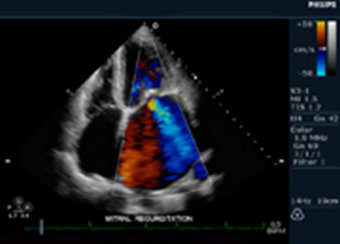

Insuficiencia mitral, dilatación auricular izquierda